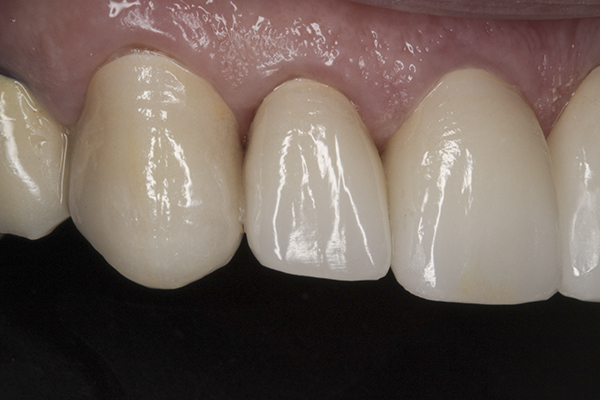

(38.) Postoperative right anterior, close-up view.

Figure 38